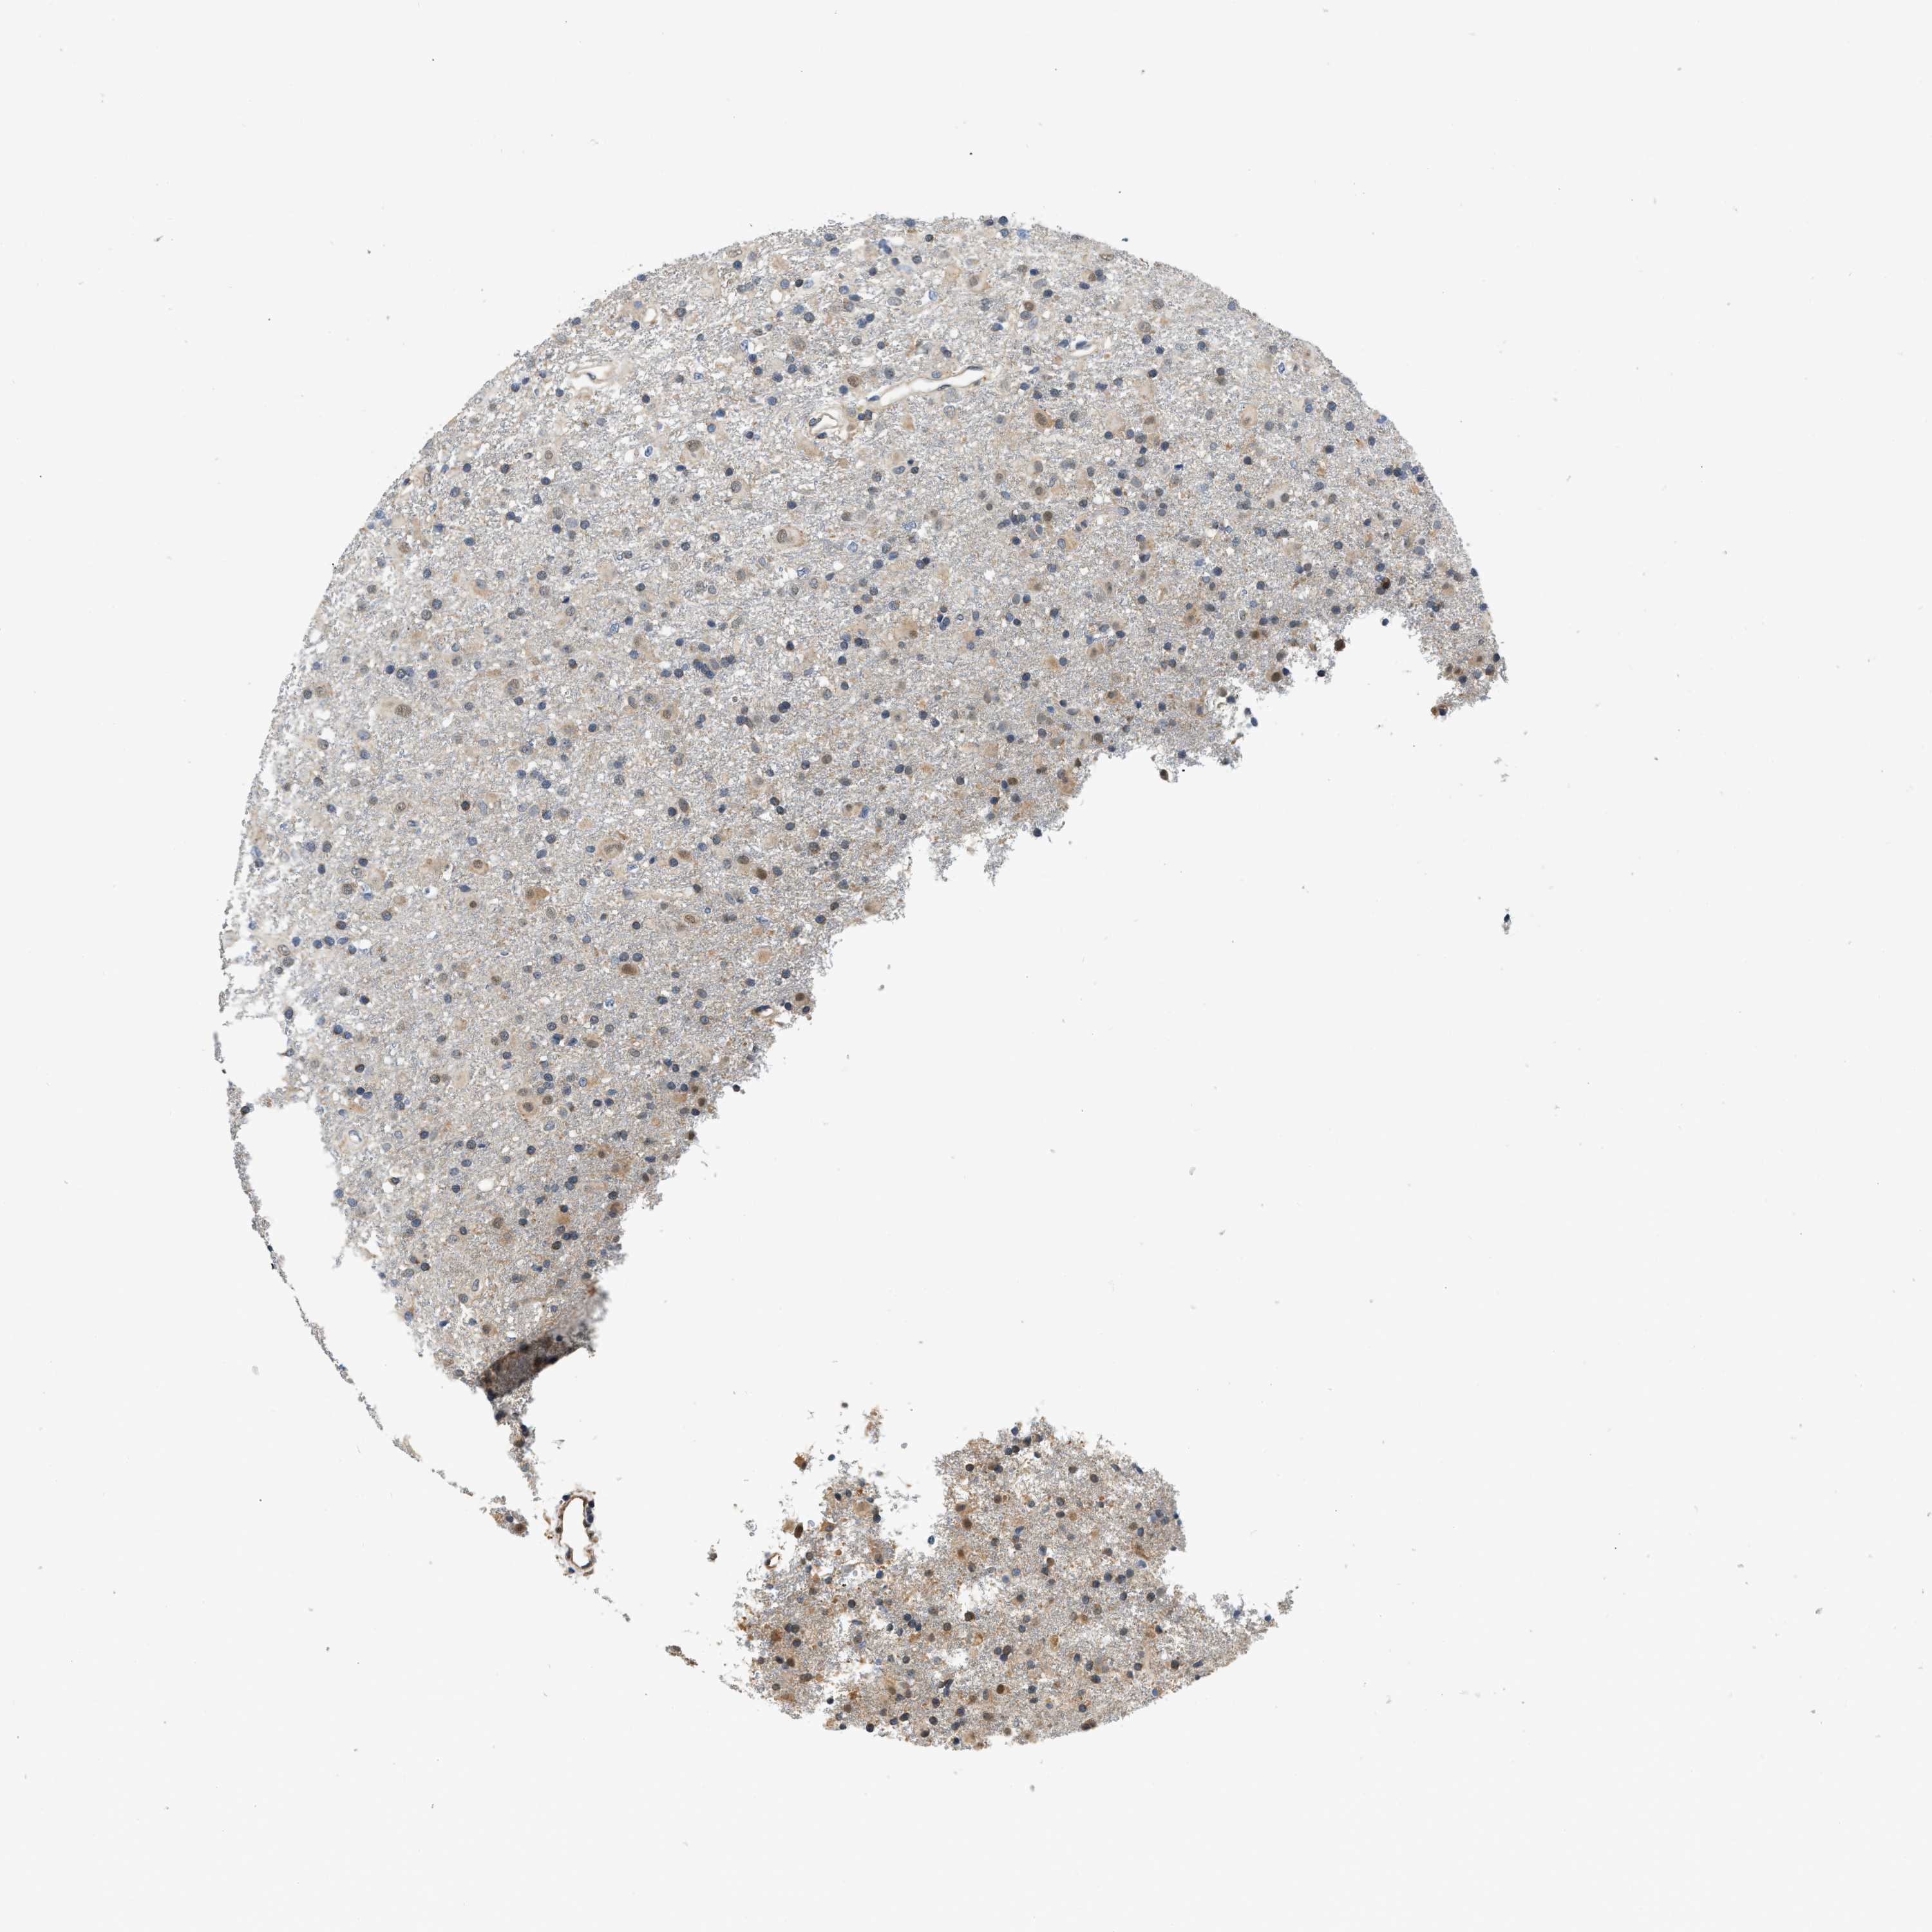

GLIOMA - Protein expressioni

A mouse-over function shows sample information and annotation data. Click on an image to view it in a full screen mode. Samples can be filtered based on level of antibody staining by selecting one or several of the following categories: high, medium, low and not detected. The assay and annotation is described here.

Note that samples used for immunohistochemistry by the Human Protein Atlas do not correspond to samples in the TCGA dataset.

Antibody stainingi

Antibody staining in the annotated cell types in the current human tissue is reported as not detected, low, medium, or high, based on conventional immunohistochemistry profiling in selected tissues. This score is based on the combination of the staining intensity and fraction of stained cells.

Each image is clickable and will lead to virtual microscopy that enables deeper exploration of all samples and also displays staining intensity scores, fraction scores and subcellular localization as well as patient and tissue information for each sample.

Antibody HPA018676

Staining

High

Medium

Low

Not detected

Intensity

Strong

Moderate

Weak

Negative

Quantity

>75%

75%-25%

<25%

None

Location

Nuclear

Cytoplasmic/membranous

Cytoplasmic/membranous,nuclear

Glioma, malignant, High grade

Glioma, malignant, Low grade